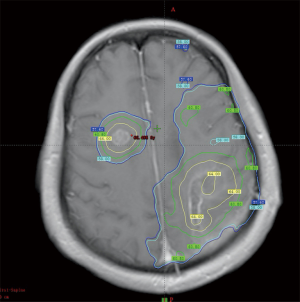

A 51-year-old female patient presented with right-limb paralysis as onset. In June 2016, T1-enhanced magnetic resonance imaging (MRI) of the head showed an abnormally enhanced occupancy signal in the left parietal and right frontal areas. Moreover, in July 2016, the left parietal lesion was surgically removed and pathologically confirmed as GBM (World Health Organization, grade IV). A postsurgery Gd-enhanced T1-weighted MRI was performed, as shown in Figure 1. She then received a postoperative 6-week intensity-modulated radiation therapy (IMRT) during which temozolomide [75 mg/m2, once daily (qd)] chemotherapy was synchronized. The IMRT was arranged as follows. In the first phase, radiation was given 2 cm outside the range of fluid attenuated inversion recovery (FLAIR) abnormal signal at an exposure extent of 40 Gy/20 f. This was followed by an MRI re-examination with a simultaneous integrated boost technique conducted for a right frontal lesion in the range where the T1 was enhanced. Moreover, the left parietal lesions within the surgical cavity were irradiated at 24 Gy/10 f, with simultaneous radiation to the area with FLAIR abnormal signal at 18 Gy/10 f. The dose distribution is shown in Figure 2. After 3 weeks of concurrent chemoradiotherapy, the patient was admitted to the hospital again due to severe headache and frequent seizures. No significant improvement was observed in the symptomatic treatment therapy of mannitol plus dexamethasone for 1 week. Enhanced T1-enhanced MRI scan showed that the abnormally enhanced range of the original left parietal and right frontal lesions significantly increased compared with that before radiotherapy, as shown in Figure 3. After fusion of the T1-enhanced MRI with the IMRT dose distribution image, the right frontal and left parietal abnormality enhancement signals were found to lay entirely within the 90% prescription dose field, as shown in Figure 4. The postoperative molecular pathological results showed that the O6-methylguanine-DNA methyltransferase (MGMT) promoter methylation was positive in the left parietal lesion. After a multidisciplinary team discussion, the patient was diagnosed with pseudoprogression after chemoradiotherapy. Continuous temozolomide monotherapy chemotherapy (250 mg/m2 days 1–5 q28d) was given as originally planned due to the poor result of previous dexamethasone treatment. Apatinib, as the concurrent treatment therapy, was given to the patient at a dose of 500 mg qd. During this treatment, symptoms of headache and rapid onset of seizures disappeared immediately. After 1 week of treatment with apatinib, MRI examination showed that the scope of the original abnormally enhanced signal was significantly reduced and the peripheral edema was alleviated compared with the images before treatment, as shown in Figure 3. The patient was treated with apatinib (500 mg qd) for 8 weeks, during which the drug was well tolerated and the patient did not show serious adverse effects to apatinib therapy. MRI scan showed no significant abnormally enhanced signal in the area of the primary lesion 14 months after the surgery (in September 2017), supporting the diagnosis of pseudoprogression after initial radiotherapy and chemotherapy, as shown in Figure 3.